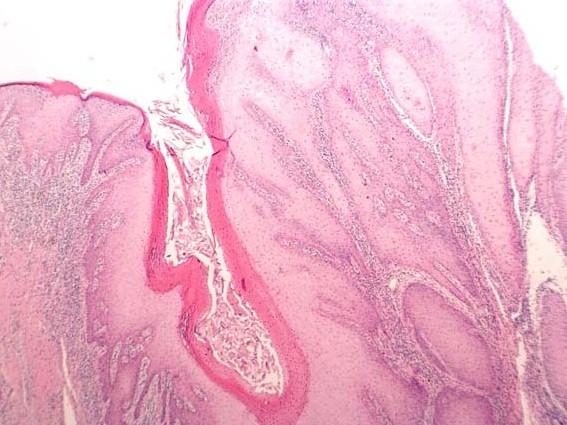

115例T1-T2期口腔鳞状细胞癌患者的临床病理参数、复发情况、局部区域及远处转移情况

Clinicopathological parameters, recurrence, locoregional and distant metastasis in 115 T1-T2 oral squamous cell carcinoma patients.

The incidence of oral squamous cell carcinoma remains high. Oral and oro-pharyngeal carcinomas are the sixth most common cancer in the world. Several clinicopathological parameters have been implicated in prognosis, recurrence and survival, following oral squamous cell carcinoma. In this retrospective analysis, clinicopathological parameters of 115 T1/T2 OSCC were studied and compared to recurrence and death from tumour-related causes. The study protocol was approved by the Joint UCL/UCLH committees of the ethics for human research. The patients' data was entered onto proformas, which were validated and checked by interval sampling. The fields included a range of clinical, operative and histopathological variables related to the status of the surgical margins. Data collection also included recurrence, cause of death, date of death and last clinic review. Causes of death were collated in 4 categories (1) death from locoregional spread, (2) death from distant metastasis, (3) death from bronchopulmonary pneumonia, and (4) death from any non-tumour event that lead to cardiorespiratory failure. The patients' population comprised 65 males and 50 females. Their mean age at the 1st diagnosis of OSCC was 61.7 years. Two-thirds of the patients were Caucasians. Primary sites were mainly identified in the tongue, floor of mouth (FOM), buccal mucosa and alveolus. Most of the identified OSCCs were low-risk (T1N0 and T2N0). All patients underwent primary resection +/- neck dissection and reconstruction when necessary. Twenty-two patients needed adjuvant radiotherapy. Pathological analysis revealed that half of the patients had moderately differentiated OSCC. pTNM slightly differed from the cTNM and showed that 70.4% of the patients had low-risk OSCC. Tumour clearance was ultimately achieved in 107 patients. Follow-up resulted in a 3-year survival of 74.8% and a 5-year survival of 72.2%. Recurrence was identified in 23 males and 20 females. The mean age of 1st diagnosis of the recurrence group was 59.53 years. Most common oral sites included the lateral border of tongue and floor of mouth. Recurrence was associated with clinical N-stage disease. The surgical margins in this group was evaluated and found that 17 had non-cohesive invasion, 30 had dysplasia at margin, 21 had vascular invasion, 9 had nerve invasion and 3 had bony invasion. Severe dysplasia was present in 37 patients. Tumour clearance was achieved in only 8 patients. The mean depth of tumour invasion in the recurrence group was 7.6 mm.An interesting finding was that 5/11 patients who died of distant metastasis had their primary disease in the tongue. Nodal disease comparison showed that 8/10 patients who died of locoregional metastasis and 8/11 patients who died from distant metastasis had clinical nodal involvement. Comparing this to pathological nodal disease (pTNM) showed that 10/10 patients and 10/11 patients who died from locoregional and distant metastasis, respectively, had nodal disease. All patients who died from locoregional and distant metastasis were shown to have recurrence after the primary tumour resection. Squamous cell carcinoma of the oral cavity has a poor overall prognosis with a high tendency to recur at the primary site and extend to involve the cervical lymph nodes. Several clinicopathological parameters can be employed to assess outcome, recurrence and overall survival.

口腔鳞状细胞癌的发病率仍然很高。口腔癌和口咽癌是全球第六大常见癌症。口腔鳞状细胞癌发生后,一些临床病理参数与预后、复发和生存率相关。在这项回顾性分析中,研究了115例T1/T2期口腔鳞状细胞癌的临床病理参数,并将其与肿瘤相关原因导致的复发和死亡情况进行比较。该研究方案已获得伦敦大学学院/大学学院医院人类研究伦理联合委员会的批准。患者数据被录入表格,并通过间隔抽样进行验证和检查。这些领域包括一系列与手术切缘状态相关的临床、手术和组织病理学变量。数据收集还包括复发情况、死亡原因、死亡日期和最后一次临床复查。死亡原因分为4类:(1) 局部区域扩散导致的死亡;(2) 远处转移导致的死亡;(3) 支气管肺炎导致的死亡;(4) 任何导致心肺功能衰竭的非肿瘤事件导致的死亡。患者群体包括65名男性和50名女性。他们首次诊断为口腔鳞状细胞癌时的平均年龄为61.7岁。三分之二的患者为白种人。原发部位主要位于舌、口底、颊黏膜和牙槽。大多数确诊的口腔鳞状细胞癌为低风险(T1N0和T2N0)。所有患者均接受了原发灶切除,必要时进行颈部清扫和重建。22例患者需要辅助放疗。病理分析显示,一半的患者患有中度分化的口腔鳞状细胞癌。pTNM与cTNM略有不同,显示70.4%的患者患有低风险口腔鳞状细胞癌。最终107例患者实现了肿瘤清除。随访结果显示3年生存率为74.8%,5年生存率为72.2%。23名男性和20名女性出现复发。复发组首次诊断时的平均年龄为59.53岁。最常见的口腔部位包括舌外侧缘和口底。复发与临床N分期疾病相关。对该组的手术切缘进行评估,发现17例有非粘连性浸润,30例切缘有发育异常,21例有血管浸润,9例有神经浸润,3例有骨浸润。37例患者存在重度发育异常。仅8例患者实现了肿瘤清除。复发组肿瘤浸润的平均深度为7.6毫米。一个有趣的发现是,11例死于远处转移的患者中有5例原发疾病位于舌部。淋巴结疾病比较显示,10例死于局部区域转移的患者中有8例以及11例死于远处转移的患者中有8例有临床淋巴结受累。将此与病理淋巴结疾病(pTNM)进行比较显示,分别死于局部区域和远处转移的10例患者和11例患者中有10例有淋巴结疾病。所有死于局部区域和远处转移的患者在原发肿瘤切除后均出现复发。口腔鳞状细胞癌总体预后较差,在原发部位复发和累及颈部淋巴结的倾向较高。可以采用一些临床病理参数来评估预后、复发和总体生存率。